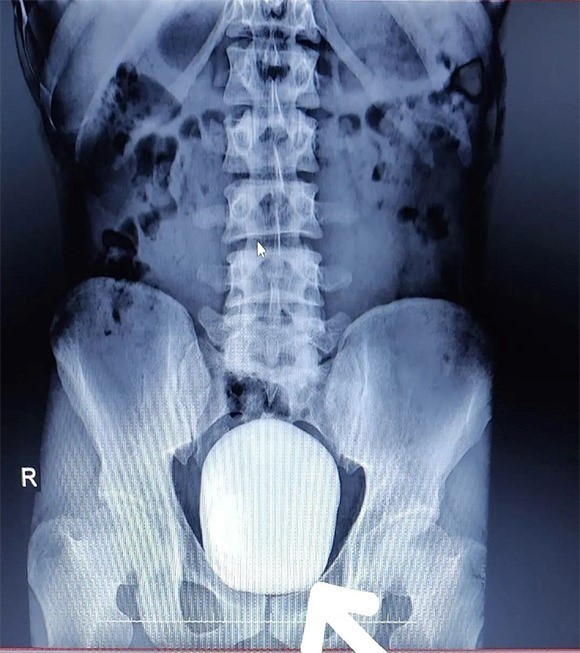

Çekilen röntgeninde hastanın mesanesinde 2 adet büyük çapta taş tespit edildi.

Doç. Dr. Güven Erbay ve Dr. Öğretim Üyesi Ahmet Şanlı tarafından yapılan cerrahi operasyonla hastanın mesanesindeki 2 taş başarılı bir şekilde alındı.

Başarılı geçen ameliyatla ilgili değerlendirmelerde bulunan Doç. Dr. Güven Erbay, "Hastanemize idrarda yanma şikayeti ile başvurdu. Yapılan tetkik ve görüntüleme sonucunda mesanesinde devasa bir taş olduğu gördük. Bunun üzerine ameliyat kararı aldık ve açık ameliyatla bu taşı aldık. Normalde mesane taşı yaşlı hastalarda ve prostatı olanlarda oluşur. Genç yaştakilerde pek beklediğimiz bir durum değildir. Başarılı geçen ameliyatın sonunda hastamızın mesanesinden 15 ve 5 santim boyutunda 2 tane taş çıkardık. Hastamızın sağlığı gayet iyi durumdadır. Şu ana kadar bilinen ve bizim de bildiğimiz kadarıyla bir hastadan çıkarılan taş bin 900 gram ağırlığındaydı. Bizim çıkardığımız 2 taşın ağırlığını ölçtüğümüzde bin 50 gram geldi. Bizim bildiğimiz üzere bu çıkarılan taşın Türkiye sınırlarında şimdiye kadar mesaneden çıkarılan en büyük taş olduğunu düşünmekteyiz" dedi.